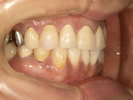

30代女性

事故のため、前歯を2本失いました。

インプラントと矯正治療をしました。

![]() |

| 治療前 | ||

| インプラント後、仮歯を入れました。 | ||

| 矯正設置を着用し、歯列矯正を行いました。 | ||

| 治療後 | ||